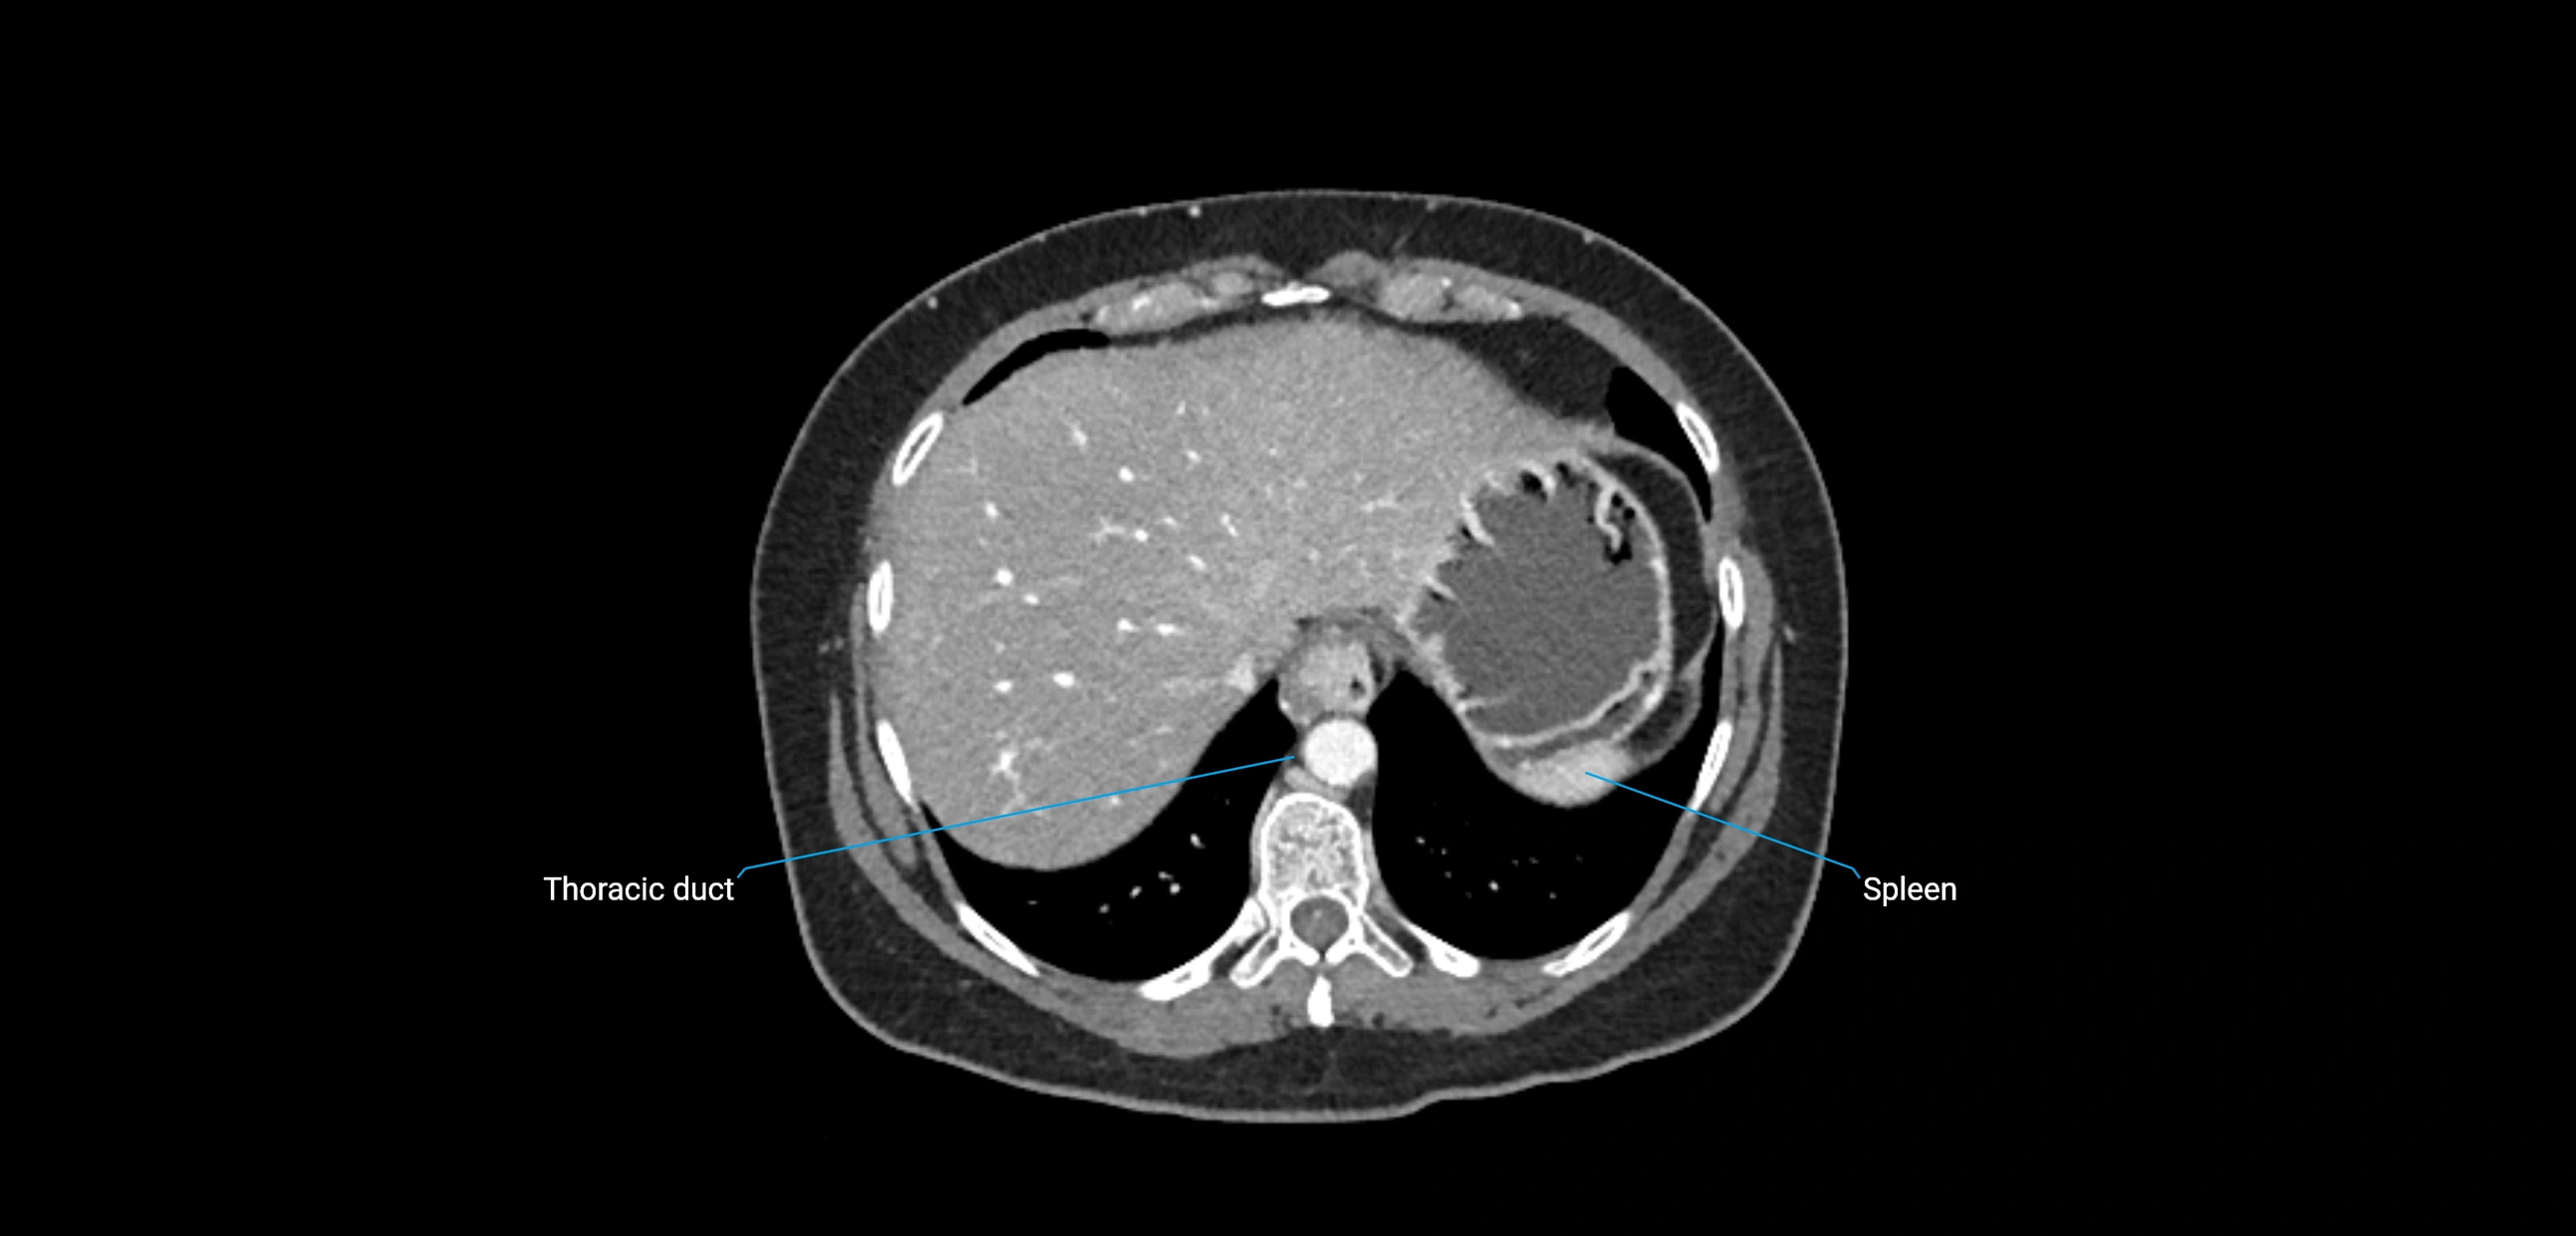

CT Appearance

CT Pre-Contrast:

• Nodes appear as soft-tissue density nodules adjacent to the aorta and IVC

• Calcification may be seen in chronic infections (e.g., tuberculosis)

CT Post-Contrast:

• Normal nodes enhance homogeneously

• Malignant nodes may show heterogeneous enhancement, central necrosis, or conglomerate formation

• Size >1 cm short axis is suspicious, though morphology and distribution are equally important